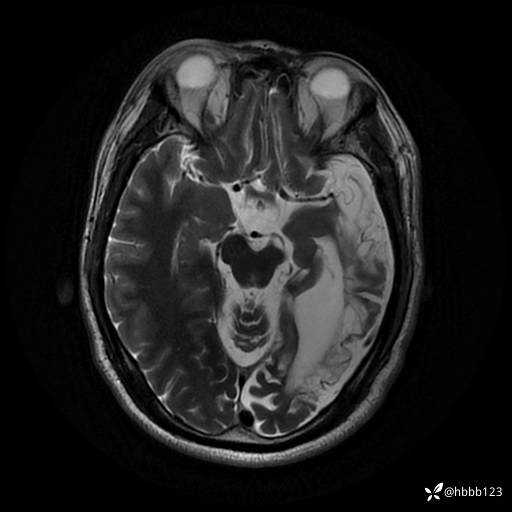

T2: